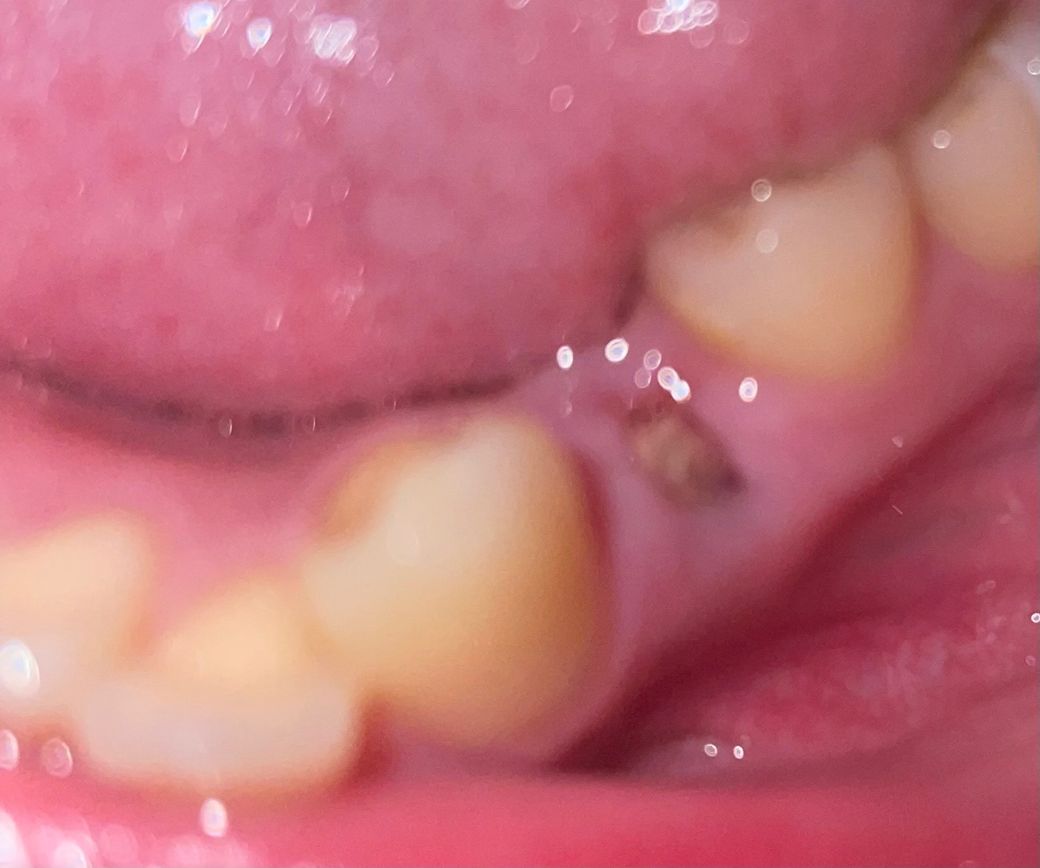

발치후 5일차 갈색 덩어리가 떨어져나가려 하고 갑자기 욱신거려요

교정때문에 발치했는데 4일차부터 갑자기 조금씩 욱신거려서 혀로 조금 건드렸는데 막 떨어지려고해요 혀로 건 든 이유로 통증이 더 심해졌어요 이거 드라이소켓아니죠? 빨대도 많이 사용 하고 술 담배도 해서 너무 걱정돼요

• 1번 째 사진

드라이소켓이라면 지금 질문자님이 말씀하신 통증보다 훨씬 강하게 옵니다. 또한 드라이소켓은 2~3일 정도에 나타나게 되며 4~5일이 지났다면 드라이소켓이 아닌 일부 혈병이 떨어지면서 발생한 통증일 수 있습니다. 해당 사진에서는 정상적인 회복과정으로 보여지므로 조금 더 지켜보시는 것을 권해드립니다. 만약 지속적으로 통증이 나타나거나 통증의 강도가 커진다면 반드시 치과를 다시 방문하는 것이 좋습니다.